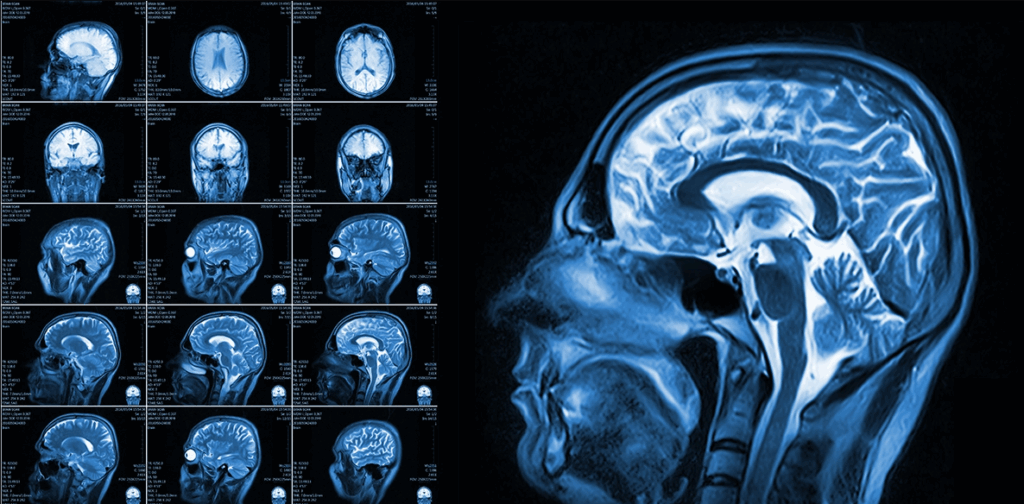

Different Types of Brain MRI Scans

Standard Brain MRI This basic scan provides detailed images of brain structure and can detect tumors, strokes, and other abnormalities.